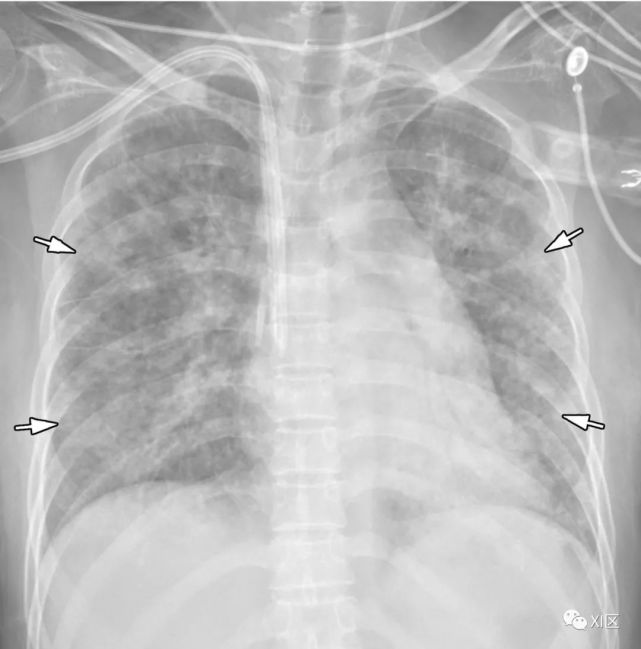

图19 52岁男性,汉坦病毒感染,因发烧及急性肾功能衰竭就诊。最初的胸部CT表现正常(未显示)。患者在就诊后1天,突然血压下降,胸片显示肺水肿和双侧胸腔积液(*)。汉坦病毒抗体检测结果为阳性,滴度提高到1:512。进行了强化治疗,病人康复。

Koo H J , Lim S , Choe J , et al. Radiographic and CT Features of Viral Pneumonia[J]. Radiographics, 2018, 38(3):719-739.